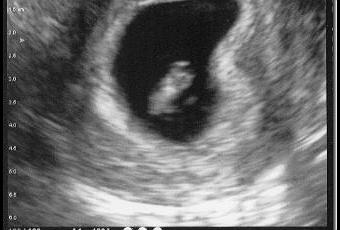

Tout a commencé par un pipi matinal bien particulier … puis sur un écran de télé une petite cacahuète avec une petite tache qui clignote.

Et oui nous allons être parents !! (Nan c’est pas un tit chien, ni un ornithorynque … enfin je crois)

Pour l’instant son arrivée est prévu dans les alentours du 19 juin 2011.